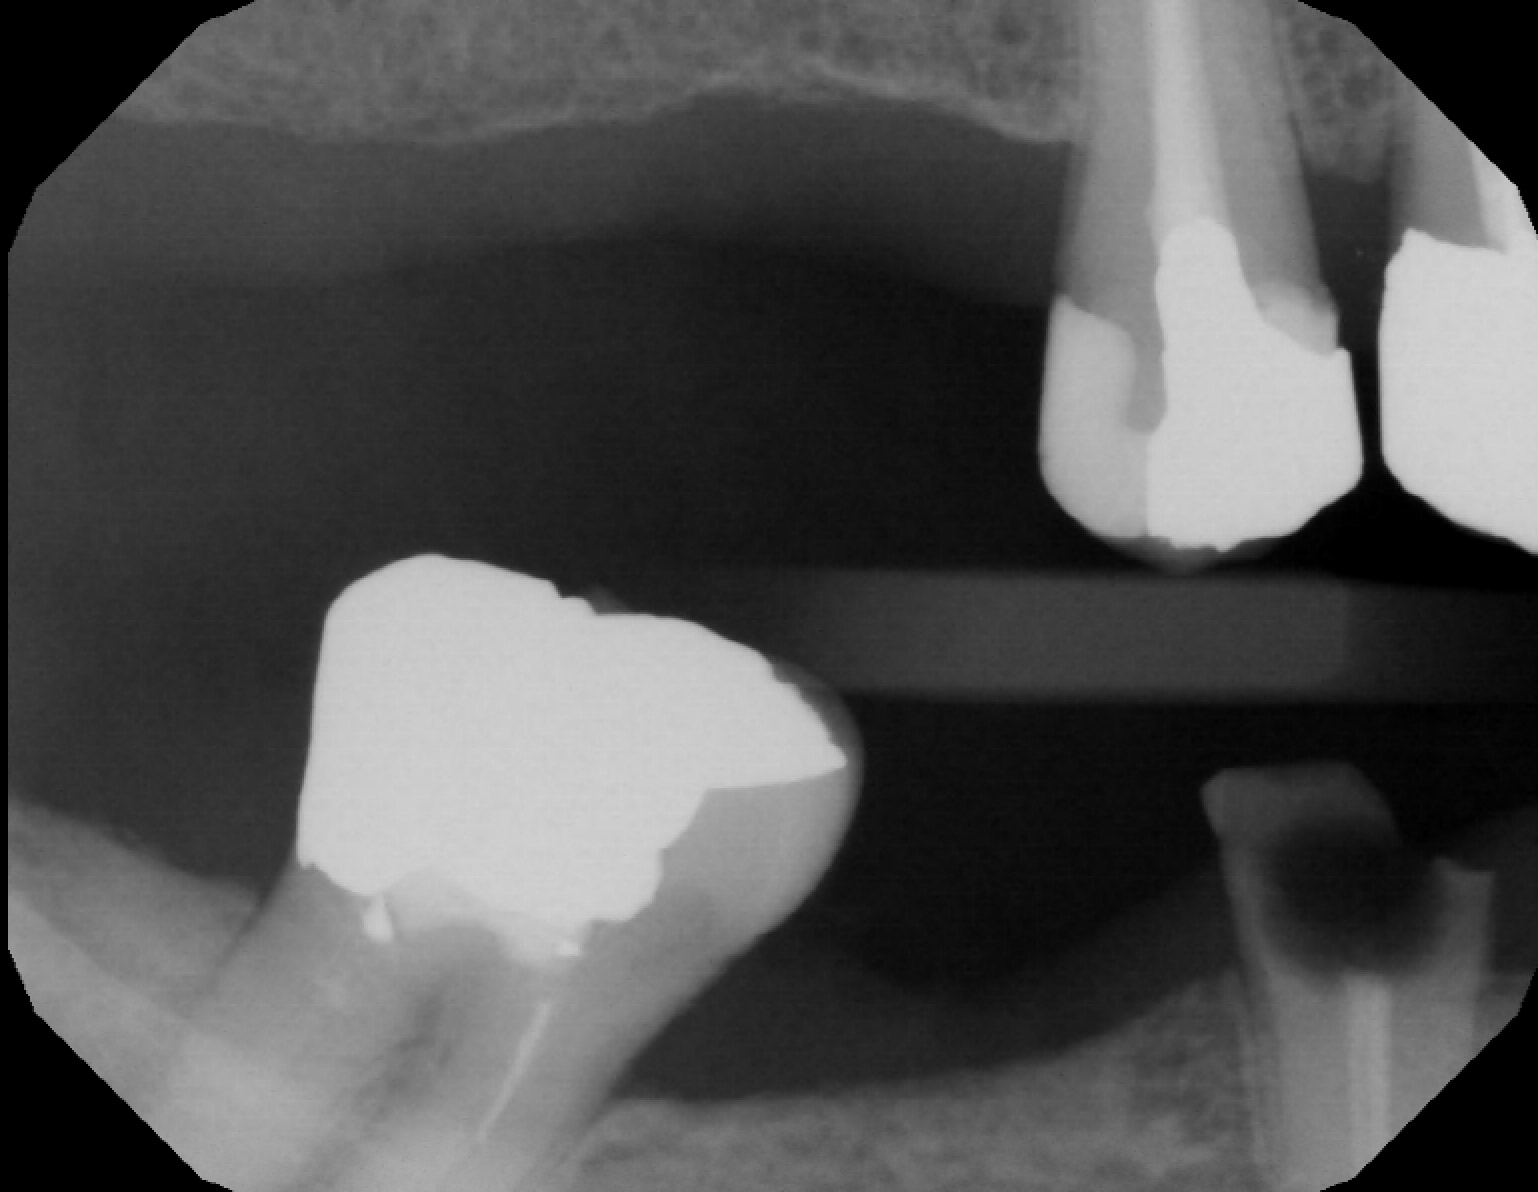

Intra Oral Pictures (1)

(Treatment in progress)

IX. RADIOGRAPHS

Note: 11 (US # 8) and 21 (US # 9) have caries into the pulp and peri apical lesions

• Residual roots: 45 (US # 29). Fractured: 44 (US # 28).

• Endodontic fillings: 15, 14, 44, 45, 47* (US # 4, 5, 28, 29 and 31*)

• Periapical lesion on 11 (US # 8) and 21 (US # 9): correlates with the clinical finding of eroded teeth down to the dentin (almost the dentino-pulp junction)

• Note : The root canal on tooth 47 (US # 31) was done in Algeria and seems to have been an attempt. There is a broken instrument in one of the canals.